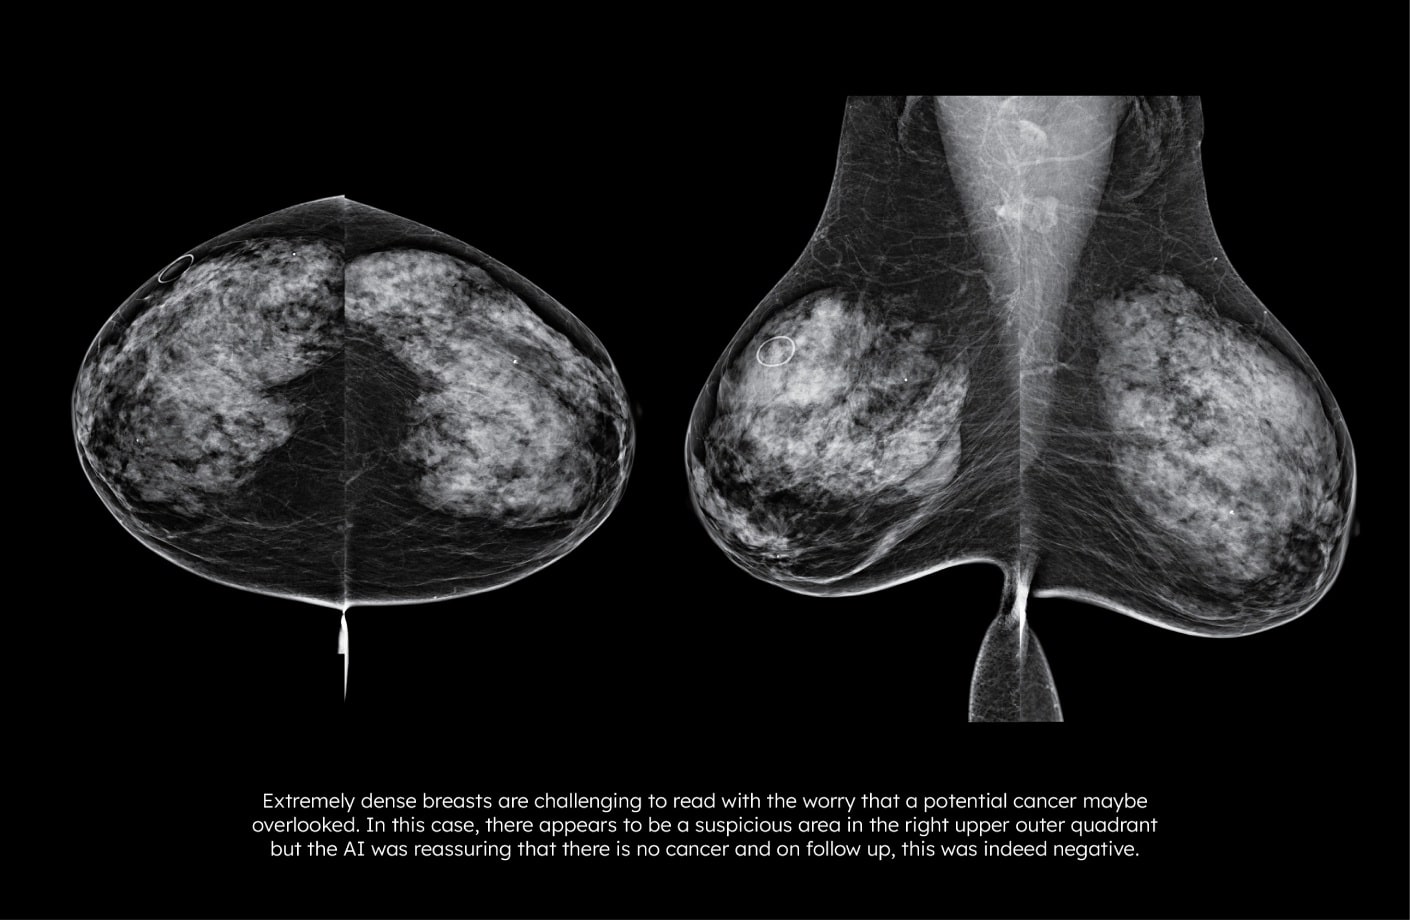

루닛 인사이트 MMG는 유방 촬영 영상을 분석해 유방암 의심부위의 위치와 유방 내 병변이 존재할 가능성을 0~100 범위의 점수로 표시합니다.

루닛 인사이트 MMG는 유방 치밀도1를 자동으로 분석합니다. BIRADS 유방밀도 A, B, C, D와 함께 각 밀도에 해당되는 AI 유방치밀도 점수(1-10)을 표시해 세분화된 분석이 가능합니다.